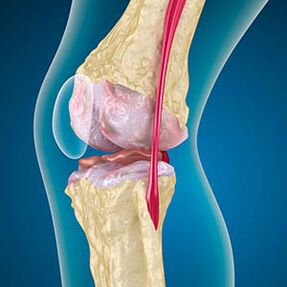

No caso da osteoartrite, a cartilaxe que lidera os bordos dos ósos é unha abrasión ou desaparecida. O tecido danado non é unha fonte de dor porque non ten receptores. A inflamación nas estruturas próximas causa síntomas característicos.

O corpo continúa a rexeneración de tecidos danados, pero a cartilaxe crece desigualmente. Como resultado, fórmanse irregularidades que violan outros elementos da articulación. O tipo de osteófito é declarado cartilaxe articular suave por compensación. Outra versión mostra que o crecemento de "Spurs"Está asociado ao intento de estabilizar a articulación nos medios ou lateralmente debido ao debilitamento muscular.

A imaxe x -ray mostra a presenza de osteófitos, un cambio no espazo entre o fémur e os ósos da tibia, o que indica a perda de cartilaxe no xeonllo. Ás veces, os raios X das articulacións do xeonllo mostran signos significativos de desgaste da cartilaxe, pero os pacientes non teñen dor significativa.Pola contra, a artrose da primeira etapa pode perturbar a función do xeonlloA causa da dor son os músculos hipotónicos.